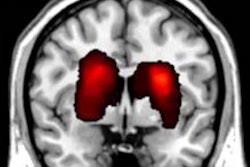

While you're in our MRI Community, be sure to check out this story on how MRI has detected abnormalities in the brain that could cause attention problems in patients who have had a stroke.